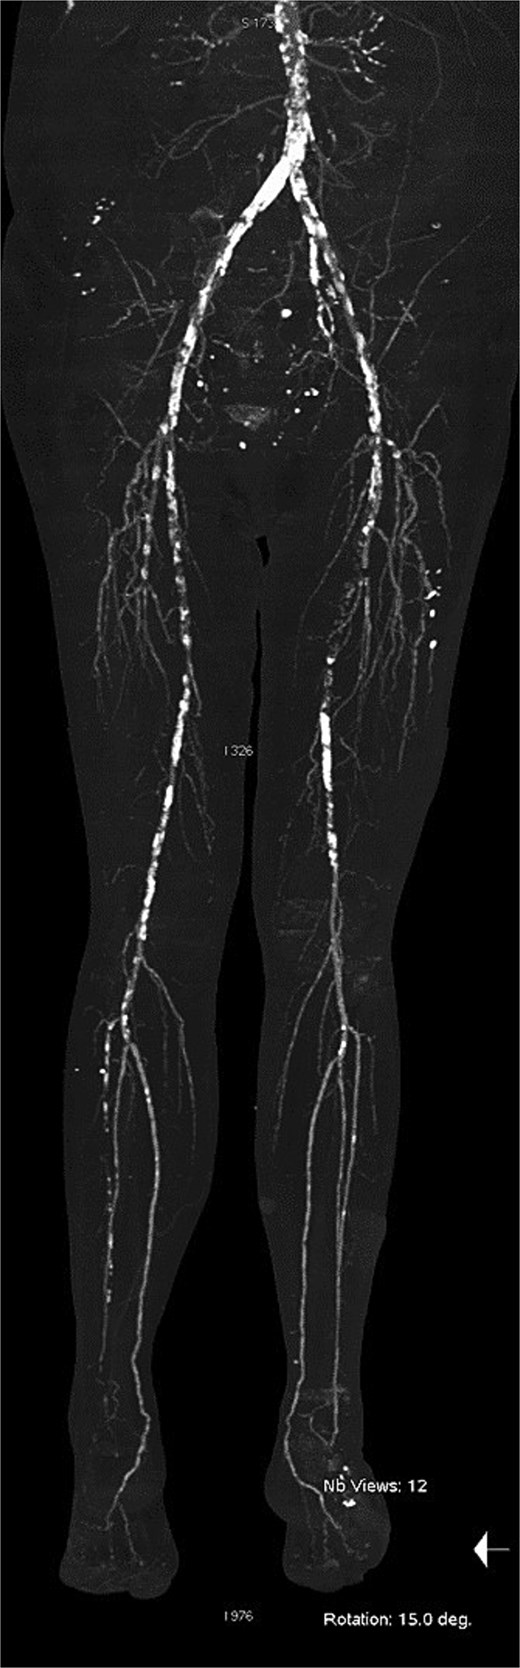

At our center, the patient underwent third to fifth toe ray amputation and subsequent anterolateral thigh free flap for soft tissue coverage (Fig. 2). The flap was initially viable, but partial necrosis developed after 3 months (Fig. 3). CT angiography revealed SFA re-occlusion (Fig. 4). Considering the limited durability of prior interventions, surgical bypass was performed. Imaging showed severe calcification of the external iliac, common femoral, and proximal SFA. She underwent femoral endarterectomy and in situ great saphenous vein bypass to the below-knee popliteal artery. Completion angiography confirmed good graft flow.